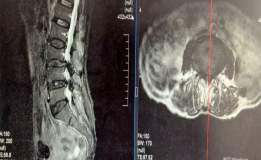

勇闯生命禁区,心脊双关创奇迹——我院疼痛脊柱科成功为77岁心脏瓣膜病患者完成高难度UBE镜下融合内固定手术

中西医协同破解老年脊柱侧弯难题,我院脊柱外科成功开展高难度开放融合手术